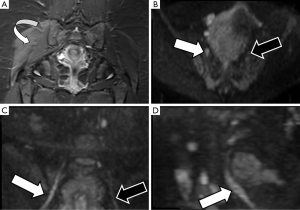

Radiation induced brachial plexus damage in oncological patients is another not uncommon clinical scenario (51). In spite of new modulated radiation therapy techniques for head and neck or breast cancer treatment, post-radiotherapy brachial plexus neuropathy has to be considered when oncological patients with suspicion of brachial plexus involvement are evaluated (Figure 8). DWN shows nerve root thickening with increased signal intensity on high b values and also increase of ADC. Moreover, in these patients, DWI has the added value to rule out malignant infiltration of brachial plexus which typically shows lower ADC values with or without associated soft tissue abnormalities. Besides, DTI through 3D neurographic reconstructions is able to demonstrate infiltration, disruption or displacement of the involved nerve roots (43).

Brachial plexus roots and trunks on DTI after a direct or an indirect trauma demonstrate similar variations of FA or RD values to those described above for PN injuries. Neuropraxia of brachial plexus roots will show a decrease of FA values, due to loss of fiber organization, and increase of RD values (Figure 9). The amount of these changes is directly related to the severity of the neural damage and may be consider as a complementary tool to the clinical and electrophysiological evaluation (52).